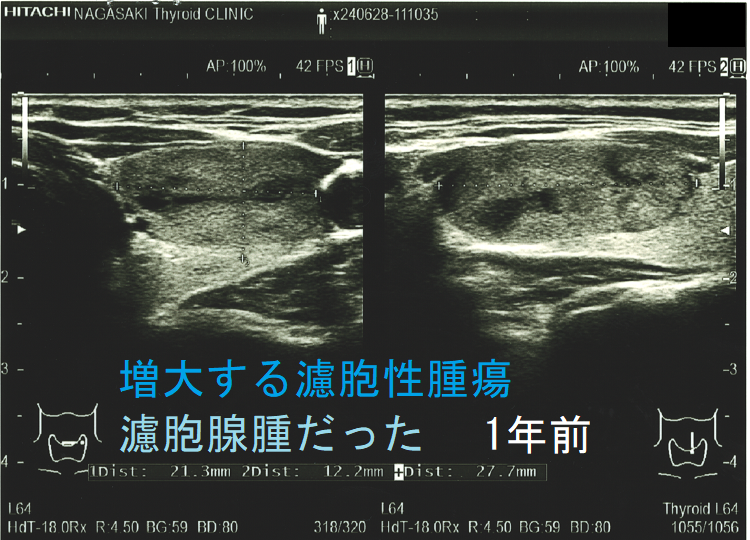

増大する濾胞性腫瘍 濾胞腺腫だった

ある意味、腫瘍の増大速度程、悪性の可能性を疑わせる所見は他にありません。急激な速度で大きくなる濾胞性腫瘍は、異常な速度で細胞増殖がおこっています。それは高い確率で甲状腺濾胞癌であると考えざる得ません。(サイズ増大で甲状腺濾胞癌と診断)